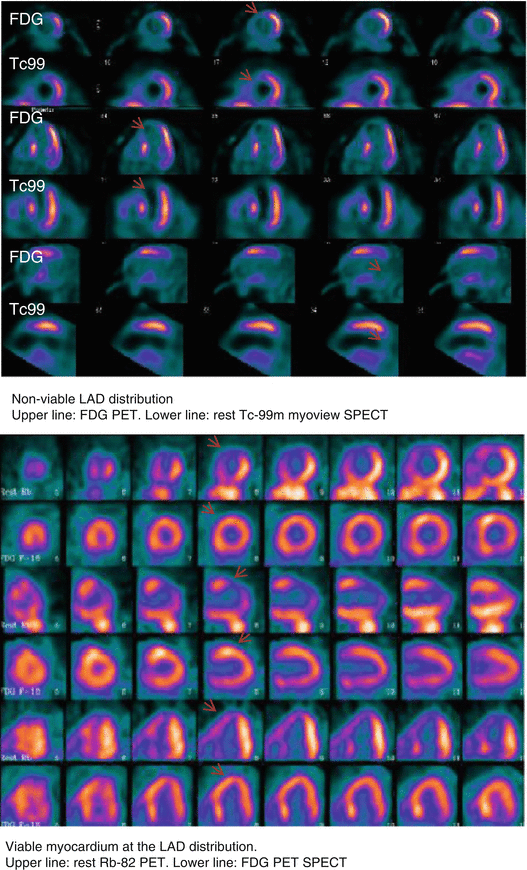

4 FDAApproved PET/CT Tracers Radiology Key Fda Approved Pet Tracers Tauvid is a radioactive diagnostic agent that binds to tau protein misfolding in the brain, a marker of alzheimer's disease. Tauvid has been approved by the u.s. In the us, clinical use of pet radiotracers is conducted under the umbrella of an fda. Tauvid has been approved by the u.s. Tauvid has been approved by the u.s. Food and drug. Fda Approved Pet Tracers.

From radiologykey.com

4 FDAApproved PET/CT Tracers Radiology Key Fda Approved Pet Tracers Tauvid is a radioactive diagnostic agent that binds to tau protein misfolding in the brain, a marker of alzheimer's disease. In the us, clinical use of pet radiotracers is conducted under the umbrella of an fda. Food and drug administration (fda) in 2020 for positron emission tomography. Tauvid™, a radioactive diagnostic agent, has been approved by the fda for positron. Fda Approved Pet Tracers.

From slideplayer.com

PET Tracers for Clinical Cardiac Imaging ppt download Fda Approved Pet Tracers Tauvid has been approved by the u.s. Tauvid is a radioactive diagnostic agent that binds to tau protein misfolding in the brain, a marker of alzheimer's disease. In the us, clinical use of pet radiotracers is conducted under the umbrella of an fda. Tauvid™, a radioactive diagnostic agent, has been approved by the fda for positron emission tomography (pet) imaging. Fda Approved Pet Tracers.